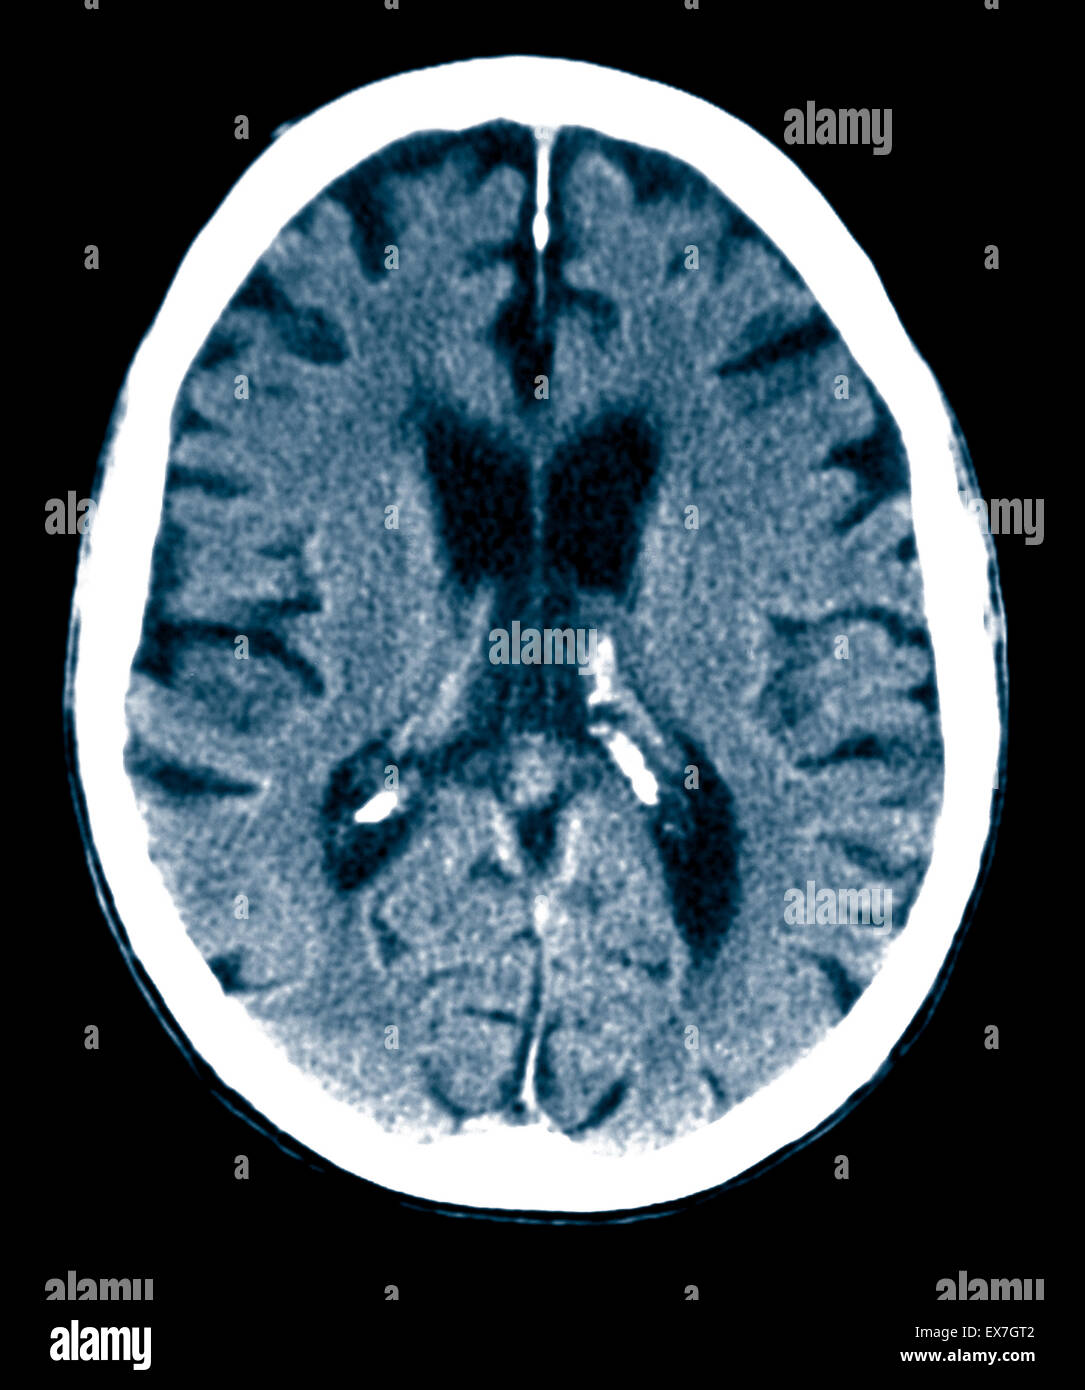

CT scan d'un vieil homme de 84 ans souffrant de la maladie d'Alzheimer. La TDM montre l'atrophie du cerveau. Banque D'Imageshttps://www.alamyimages.fr/image-license-details/?v=1https://www.alamyimages.fr/photo-image-ct-scan-d-un-vieil-homme-de-84-ans-souffrant-de-la-maladie-d-alzheimer-la-tdm-montre-l-atrophie-du-cerveau-84989410.html

CT scan d'un vieil homme de 84 ans souffrant de la maladie d'Alzheimer. La TDM montre l'atrophie du cerveau. Banque D'Imageshttps://www.alamyimages.fr/image-license-details/?v=1https://www.alamyimages.fr/photo-image-ct-scan-d-un-vieil-homme-de-84-ans-souffrant-de-la-maladie-d-alzheimer-la-tdm-montre-l-atrophie-du-cerveau-84989410.htmlRMEX7GT2–CT scan d'un vieil homme de 84 ans souffrant de la maladie d'Alzheimer. La TDM montre l'atrophie du cerveau.